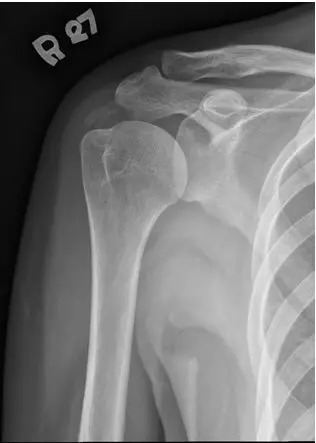

本題提供右肩的 X 光及 MRI 影像各一張:

X 光影像(圖一): 右肩(標記 R)X 光可見肱骨大結節(greater tuberosity)上方、腱板(rotator cuff)走行區域,有一明顯的圓形、緻密高密度鈣化沉積灶(calcific deposit),邊緣清晰,呈均質性高密度,位置對應棘上肌腱(supraspinatus tendon)及 subdeltoid bursa 附近。骨質本身無明顯骨侵蝕或關節間隙狹窄,無痛風石(tophus)的典型位置,符合 apatite 晶體(calcium hydroxyapatite)軟組織鈣化的典型 X 光表現。